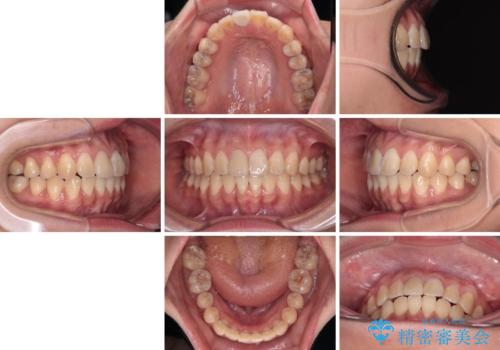

舌の突出癖による開咬と前歯の突出 インビザライン矯正治療

- 上下前歯の非接触と叢生を気にして来院された患者様です。

開咬の改善はインビザラインの最も得意とするところであるため、インビザラインを用いて矯正治療を行うこととしました。

治療開始直後に上顎前歯に激しい痛みが発現し、矯正治療を休んだり、マウスピースの装着時間を短くしたりと工夫をしましたが、残念ながら治療途中で失活していることが分かりました。

矯正治療の途中で前歯の根管治療とオールセラミッククラウンによる補綴治療を行い、その後インビザライン1セットを用いて細かい部分を仕上げました。